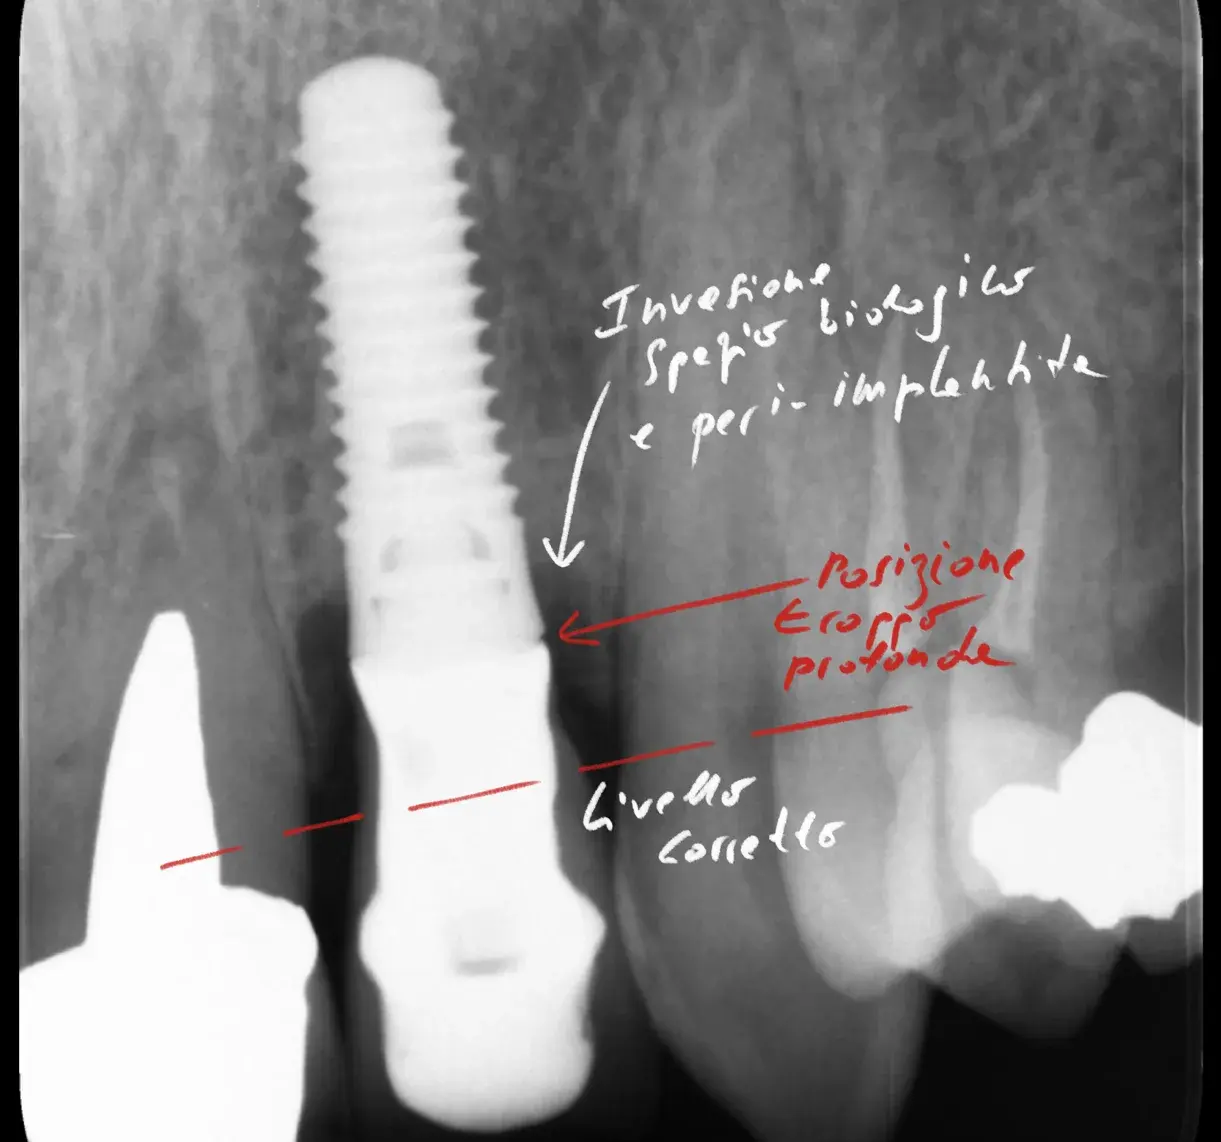

Somiglianze, differenze e meccanismi patogeni tra il microbiota della peri-implantite e quello della parodontite. Una rassegna della letteratura.